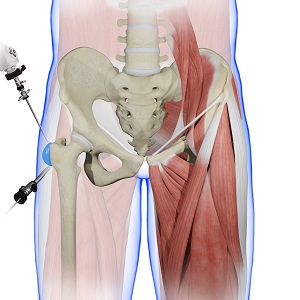

A bursectomy is the surgical removal of a bursa. An arthroscopic bursectomy is known as a trochanteric bursectomy when the greater trochanter is involved. The greater trochanter is the ridge at the top of the femur. Trochanteric bursectomy is usually performed arthroscopically as a minimally invasive procedure. An arthroscope is a small, fiber-optic instrument consisting of a lens, light source, and video camera. The camera displays images of the inside of the joint onto a monitor, allowing your surgeon to assess any damage and perform a repair.

- Arthroscopic portals are inserted through a small incision at the joint.

- Special surgical instruments are inserted through another small incision.